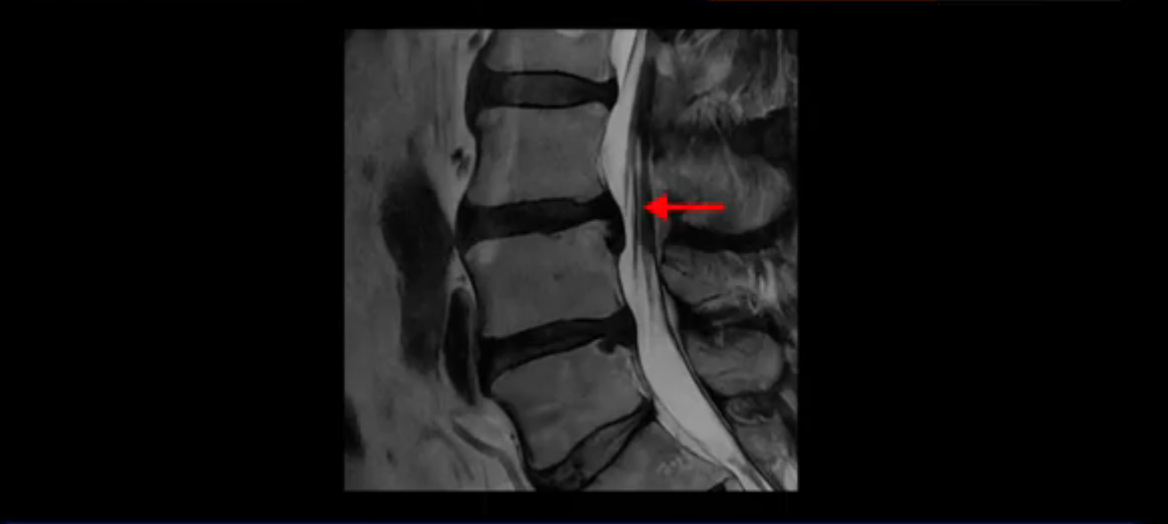

이분 MRI를 잠깐 보실까요? 보시면 두 마디가 특히 안 좋은데 3번 4번 디스크가 터져서 흘러 내려 있습니다.

보시다시피 흘러 내려온 디스크 수핵이 신경 공간의 왼쪽으로 보입니다.

그런데 이분은 4번 5번에도 디스크 파열이 있습니다.

가운데로 심하게 밀려 나와 있는데요.

또 4번 5번에는 협착으로 척추관이 많이 좁아져 있습니다.

또 왼쪽 신경 가지들이 빠져 나가는 신경구멍들이 여러 마디가 좁아져 있습니다.

이런 이유들 때문에 왼쪽 엉덩이부터 종아리, 발가락까지 저리고 아픈 겁니다. 그래서 서둘러 병원에 가셨는데요. 그래서 서둘러 병원에 가셨는데요. 여러분이 꼭 아셔야 할 게 이렇게 다리가 심하게 저리고 아프면 X-ray만 찍을 게 아니고 MRI를 찍어 보시는 게 맞습니다. X-ray로는 디스크가 터졌는지 신경구멍이 좁아진 협착이 있는지를 정확히 할 수가 없습니다. 그래서 이분은 당장 아픈데 해결이 안 되니까 제주도에서 유명하다는 한의원으로 갔습니다.